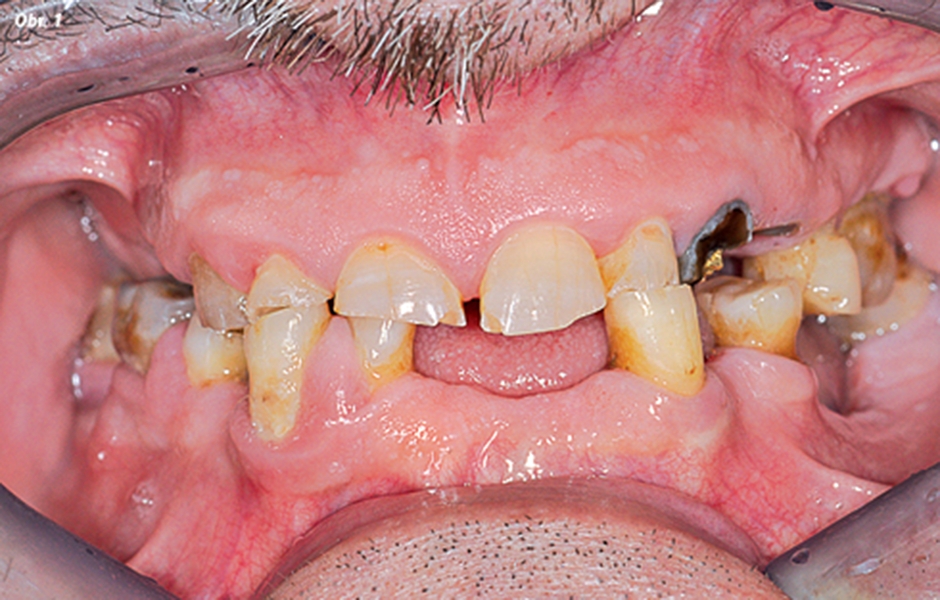

Pacient A. P. trpěl problémy s funkčností a zejména s estetikou svého chrupu s negativními psychologickými důsledky (obr. 1–3). Po provedení klinických vyšetření zubní lékař konstatoval nemožnost použití zbývajícího chrupu a rozhodl se přikročit ke zhotovení imediátních celkových snímatelných náhrad, coby přípravy na definitivní rehabilitaci chrupu nezávislé na typu opory (sliznice nebo implantát).

Frontální pohled